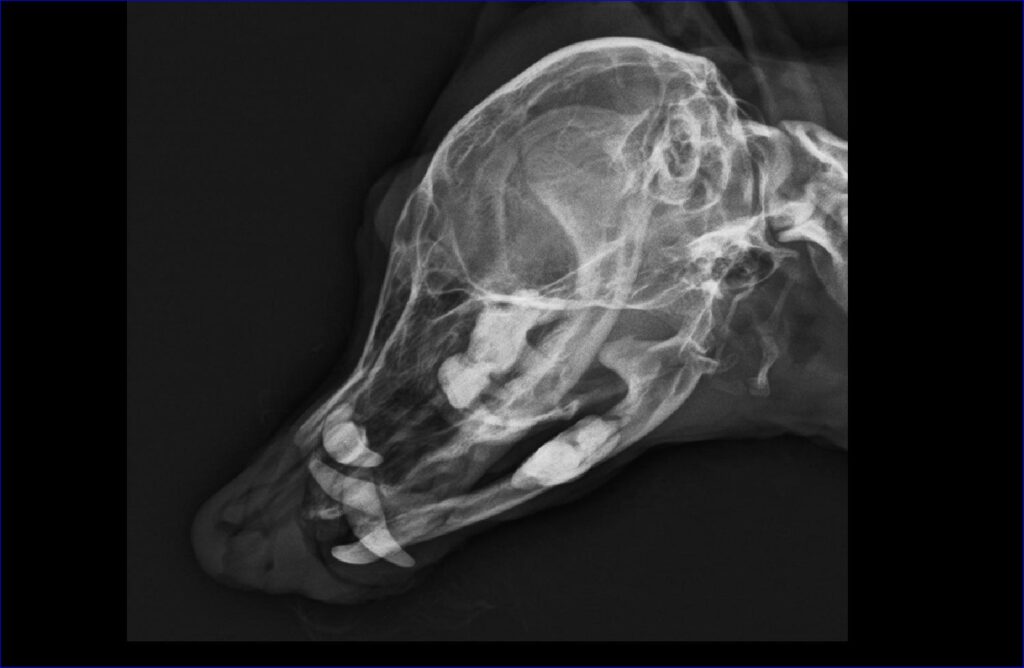

術前検査で、全身麻酔を安全に行えるかを確認します。持病がある場合や高齢の動物も、検査結果に応じて安全な対応を検討します。また、必要があれば、(特に抜歯を検討している場合は)口腔内のレントゲンやCT撮影し、歯根や顎の骨の状態を確認します。術前検査は基本的に手術当日に行います。